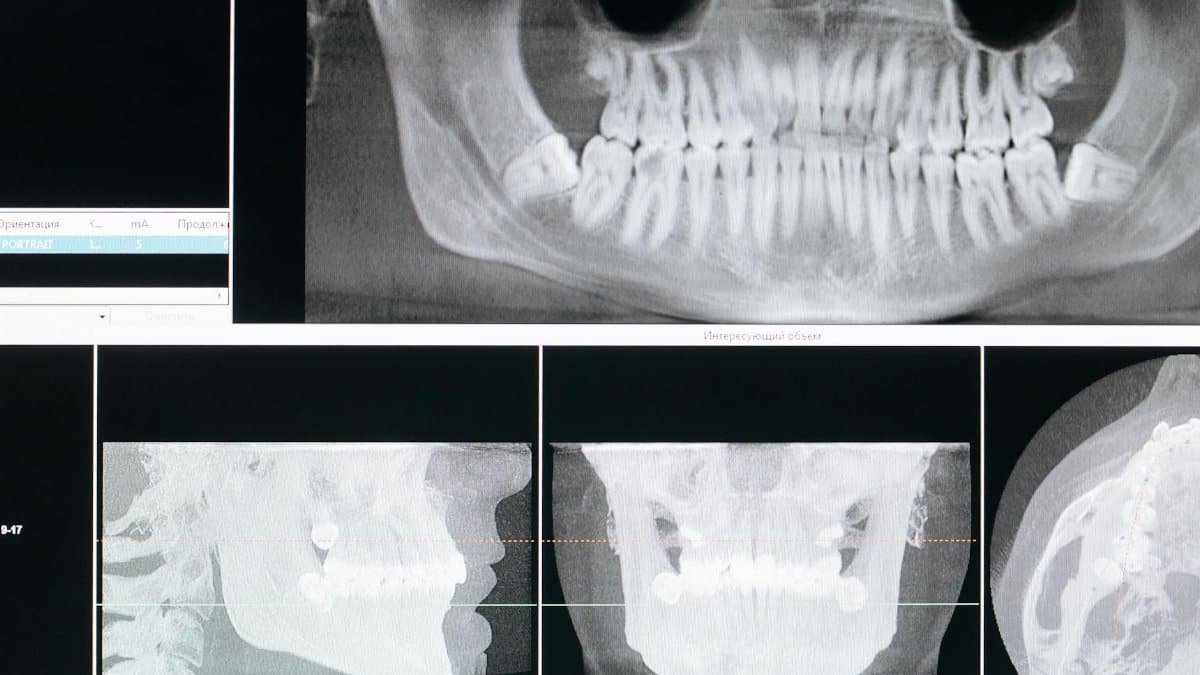

Detail image of a panoramic dental X-ray, showing teeth and jaw structure.

Photo by cottonbro studio via Pexels

New Yorkers rushing through crowded streets might not notice their jaws tightening like vises. This subtle stress signal often masquerades as a habit, but experts say it’s a direct response to mounting pressure. Dr. Emily Chen, a Manhattan-based psychologist, notes that chronic clenching can lead to headaches and even dental issues. A study from the National Institutes of Health links it to elevated cortisol levels, the body’s stress hormone. To counter it, simple mindfulness exercises like deep breathing during commutes can help. In a city that never sleeps, ignoring this could amplify anxiety over time.